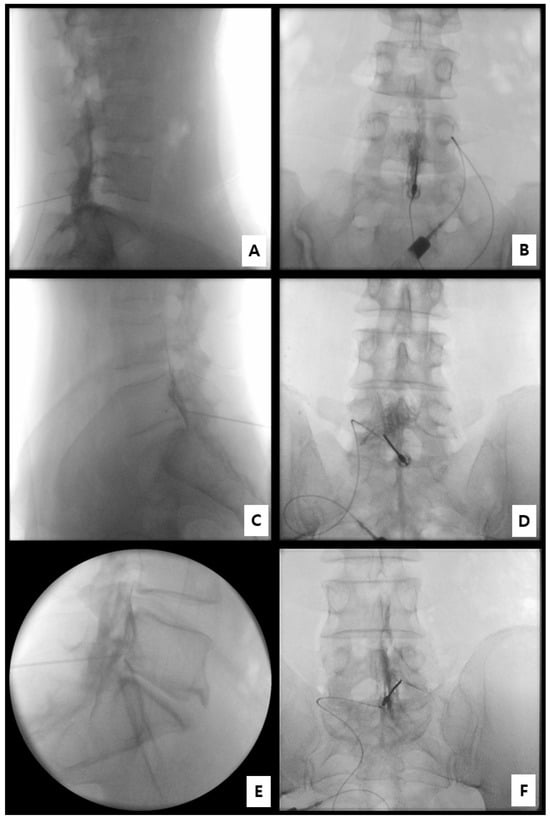

2.3. Procedural Technique for Catheter-Free LIVEI at L5–S1

- Step 1. Fluoroscopic target identification (AP)

- Step 2. Midline entry and bone docking

- Step 3. Interlaminar epidural access confirmation

- Step 4. Controlled ventral advancement (“saline cushion” technique)

- Step 5. Fluoroscopic confirmation of ventral epidural positioning

- Step 6. Final injectate delivery

2.4. Fluoroscopic Assessment and Grading of Spread

- Grade 3: Anterior (ventral) epidural spread with foraminal extension at two or more levels;

- Grade 2: Anterior spread with limited foraminal or cranio-caudal extent;

- Grade 1: Posterior-only or failed anterior spread.

3.2. Fluoroscopic Findings

| Contrast Spread Grade | Definition | N (%) |

|---|---|---|

| Grade 3 | Anterior (ventral) spread with foraminal extension involving ≥ 2 levels | 8 (66.7%) |

| Grade 2 | Anterior (ventral) spread with limited foraminal involvement | 4 (33.3%) |

| Grade 1 | Posterior-only or absence of anterior (ventral) spread | 0 (0%) |

| Total | Ventral epidural spread confirmed | 12 (100%) |